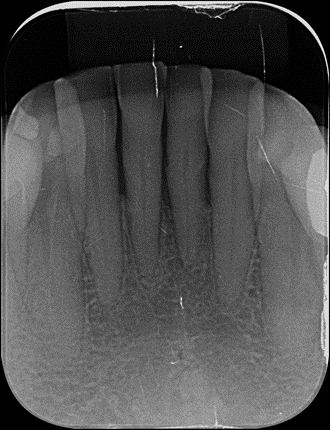

Pacientes idosos com histórico de doença periodontal avançada frequentemente apresentam perda dentária e reabsorção óssea significativa. No caso em questão, um paciente de 75 anos apresentava mobilidade acentuada e comprometimento periodontal nos incisivos inferiores centrais (dentes 31 e 41), indicando prognóstico desfavorável e a necessidade de exodontia.

A decisão pela extração dos dentes 31 e 41 baseou-se em critérios de severidade periodontal (mobilidade grau III e perda óssea vertical) e na falta de suporte adequado para manter esses elementos. A substituição por implantes imediatos foi indicada a fim de evitar a remodelação óssea excessiva pós-extração e preservar o contorno gengival papilar da região anterior. O procedimento foi meticulosamente planejado com abordagem minimamente invasiva: optou-se pela técnica sem abertura de retalho, executando exodontias minimamente traumáticas para manter intactos o periósteo e as paredes alveolares. Essa abordagem visa reduzir a invasividade cirúrgica e preservar suprimento sanguíneo periosteal, contribuindo para menor reabsorção óssea e melhor manutenção das papilas interdentais. Na literatura, a preservação dos tecidos duros e moles obtida com exodontia atraumática e instalação imediata do implante está associada à estabilidade volumétrica do rebordo alveolar, facilitando a estética das papilas e do perfil de emergência da futura prótese. Adicionalmente, ao evitar um período prolongado de edentulismo ou o uso de próteses removíveis temporárias, promove-se maior conforto e aceitação por parte da paciente, alinhando a conduta clínica às expectativas funcionais e psicológicas.

Em um primeiro momento foi feito um pequeno desgaste com ponta diamantada nas faces mesiais dos dentes 32 e 42 para aumentar o espaço mésio-distal. Com a paciente sob anestesia local adequada, procedeu-se às exodontias dos incisivos 31 e 41 utilizando técnica minimamente traumática. Realizou-se incisão intrasulcular ao redor dos dentes e uso delicado de periótomo e alavancas de pequeno porte, promovendo a luxação e remoção cuidadosa das raízes sem descolar retalhos mucoperiostais. Essa técnica conservadora preservou os tecidos peri-implantares – em especial a papila interdental entre os dentes 32 e 42 – e manteve a integridade das paredes ósseas alveolares, fundamentais para a estética e cicatrização. Confirmada a ausência de fenestrações ou deiscências ósseas pós-exodontia, prosseguiu-se imediatamente com a osteotomia para instalação dos implantes. Seguiu-se o protocolo de fresagem recomendado pelo fabricante para o implante Stretto, utilizando sequência de brocas de diâmetro incremental adequado à densidade óssea presente. O conjunto Stretto apresenta brocas desenhadas para preparos precisos e minimamente invasivos, facilitando a instalação em sítios com espaço limitado. A preparação atingiu estabilidade primária suficiente apicalmente, permitindo o travamento dos implantes nos alvéolos frescos. Foram instalados dois implantes cone morse Stretto (Ø 3,0 mm x 11,5 mm) nas posições 31 e 41, posicionados de forma centralizada nos respectivos alvéolos e com paralelismo adequado entre si. Importante notar que o implante Stretto foi desenvolvido especificamente para situações críticas de espaço protético e ósseo reduzido, combinando facilidade cirúrgica e versatilidade protética para reabilitar tais casos.